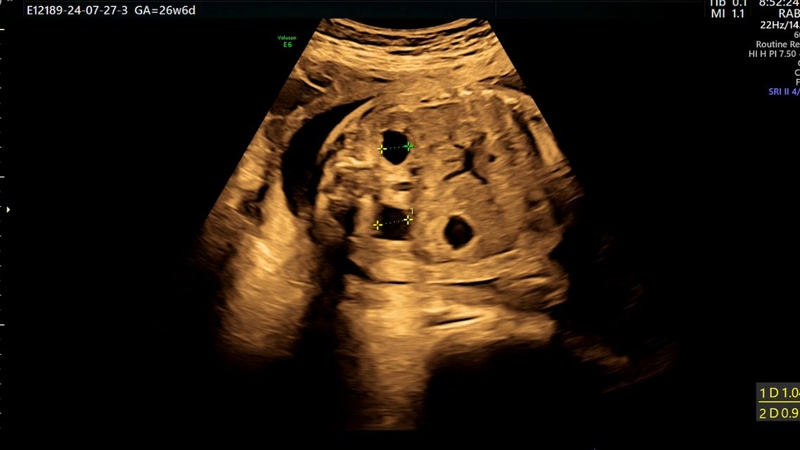

Siêu âm là phương pháp chẩn đoán chính và được khuyến nghị thực hiện vào khoảng 20 tuần thai, khi thận và hệ tiết niệu của thai nhi đã phát triển đủ để quan sát rõ ràng. Qua siêu âm, bác sĩ có thể đo các chỉ số như đường kính bể thận và độ giãn bể thận, từ đó phân loại mức độ thận ứ nước thành nhẹ, trung bình hoặc nặng.

Trong những trường hợp nghiêm trọng hoặc khi kết quả siêu âm chưa rõ ràng, bác sĩ có thể chỉ định MRI thai nhi để đánh giá chi tiết cấu trúc thận và đường tiết niệu. Ngoài ra, nếu nghi ngờ dị tật bẩm sinh hoặc bất thường di truyền, việc kiểm tra di truyền cũng có thể được thực hiện để xác định nguyên nhân và dự đoán nguy cơ.